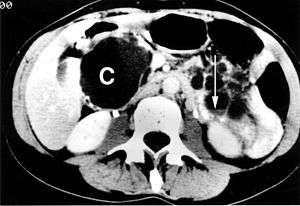

| A large pancreatic cyst at the uncinate process of the pancreas | |

A pancreatic cyst is a fluid filled sac within the pancreas.